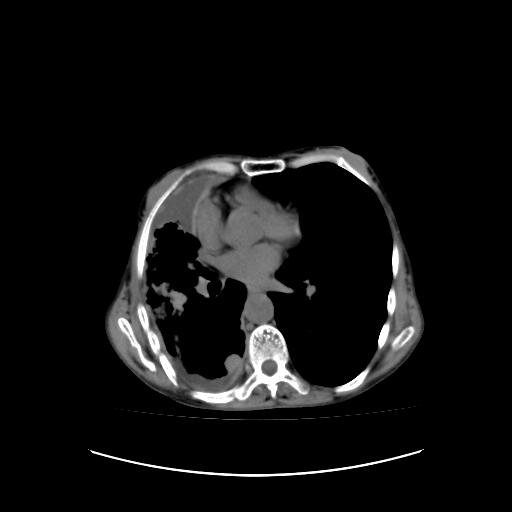

可见多发肺内病灶,且胸膜病灶较多有圆球状而非丘状,多考虑胸膜转移瘤伴胸腔积液,右侧胸廓缩小固定,且部分病灶呈丘状,尚不除外恶性胸膜间皮瘤伴肺内转移

恶性胸膜间皮瘤伴肺内转移可能性大;或胸膜、肺内均为转移瘤,左肺下叶亦见多发小结节影。

右侧胸廓塌陷,右侧胸膜广泛增厚并见多发胸膜结节,右侧少量胸腔积液并包裹。

右胸腔结节均考虑来自胸膜(部分来源于叶裂),考虑胸膜间皮瘤或转移瘤.